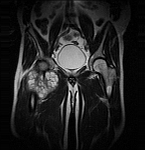

- Extensive reconstructive procedures for the reconstruction of large pelvic bone defects

- Resection of benign and malignant tumors of the bone and soft tissue